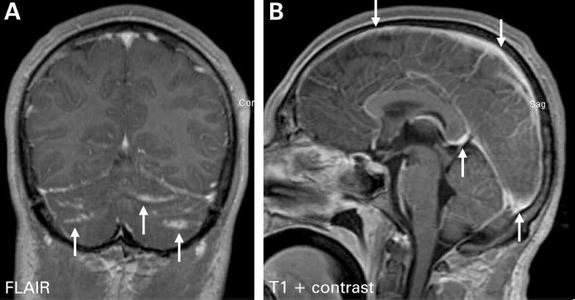

隐球菌感染的临床表现多种多样,可以包括从无症状、局限性肺部感染到播散性疾病。播散性疾病可以累及机体任何系统,最常侵犯中枢神经系统导致脑膜炎、脑膜脑炎及颅内局灶性肉芽肿。

脑膜脑炎的典型表现为严重头痛,可持续数周至数月,可伴随精神态势改变、人格改变、发热、昏睡及昏迷;其他神经系统并发症包括脑积水(交通性或非交通性)、视乳头水肿、突发感音性聋、颅神经麻痹、运动感觉障碍、小脑功能障碍和癫痫等。